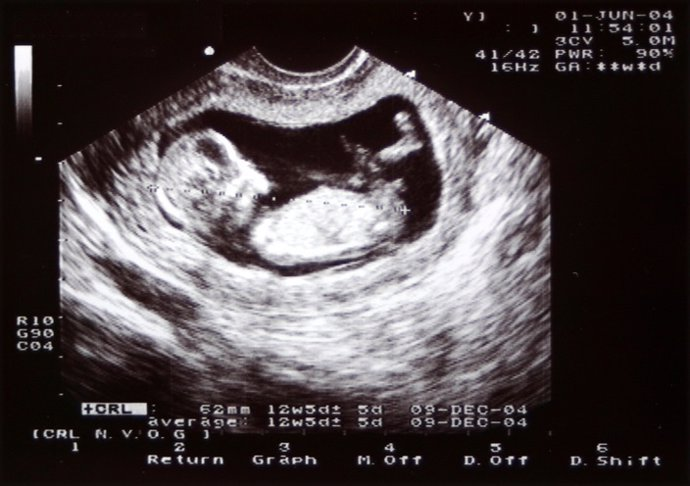

El desarrollo embrionario humano es un proceso fascinante que transforma una sola célula en un organismo completo y funcional. Este viaje comienza en el momento de la fertilización y continúa hasta el nacimiento. En este recorrido, millones de células se dividen, diferencian y organizan para formar los tejidos y órganos del cuerpo. AquÃ, te adentrarás en cada una de las etapas del desarrollo embrionario, descubriendo los eventos clave y las transformaciones que ocurren semana tras semana.

Primer Trimestre (Semanas 1-12)

- Fertilización y Segmentación: El cigoto se divide rápidamente y se implanta en el útero.

- Formación del Blastocisto y Gastrulación: El blastocisto se convierte en un embrión con tres capas germinales.

- Neurulación y Organogénesis: El tubo neural se forma y los órganos comienzan a desarrollarse. El corazón empieza a latir alrededor de la sexta semana.